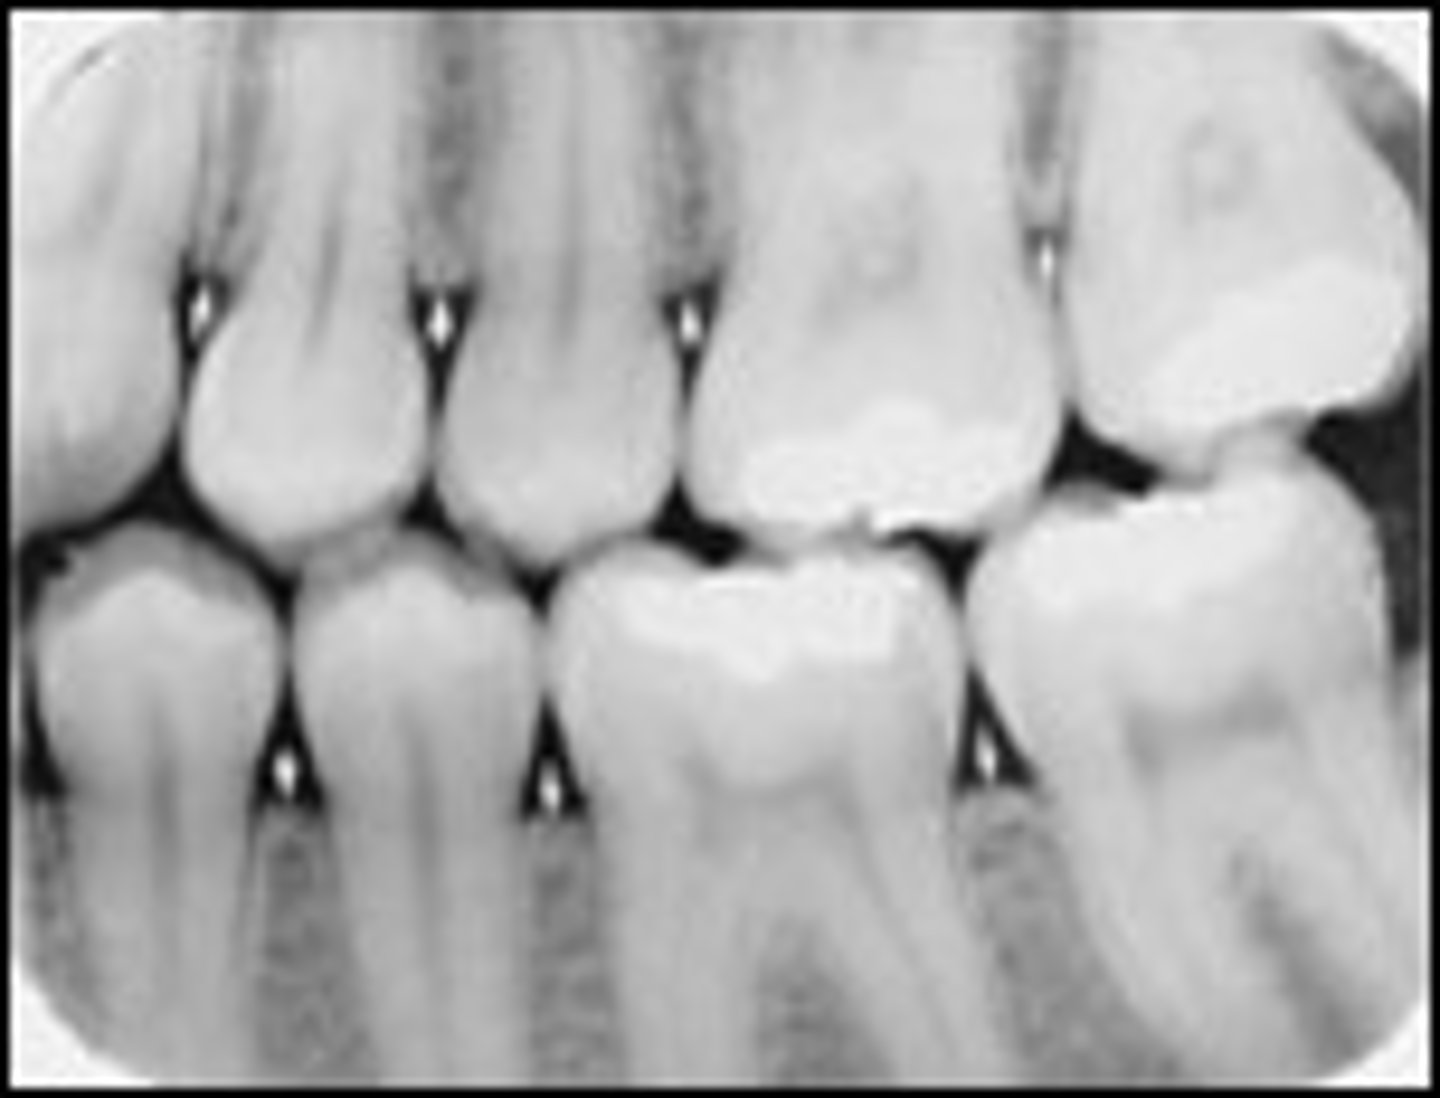

Cortical bone

What kind of bone is shown here?

Cancellous bone

Lamina dura

What is the radiopaque structure seen here?

Alveolar crest

Periodontal ligament space

What is the radiolucent structure seen here?